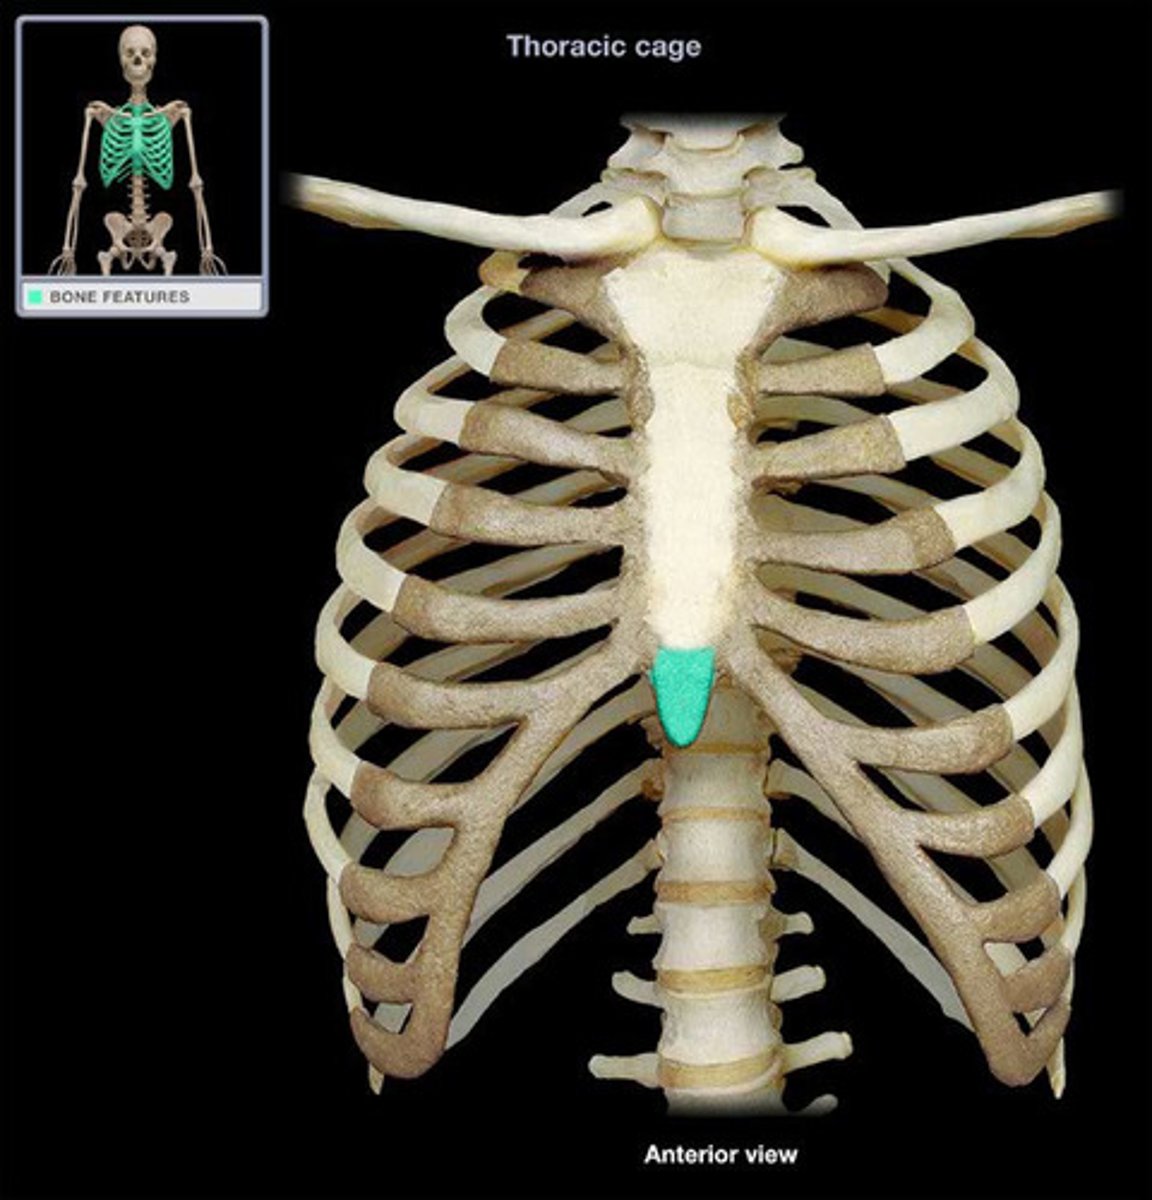

Sternum

Xiphoid Process